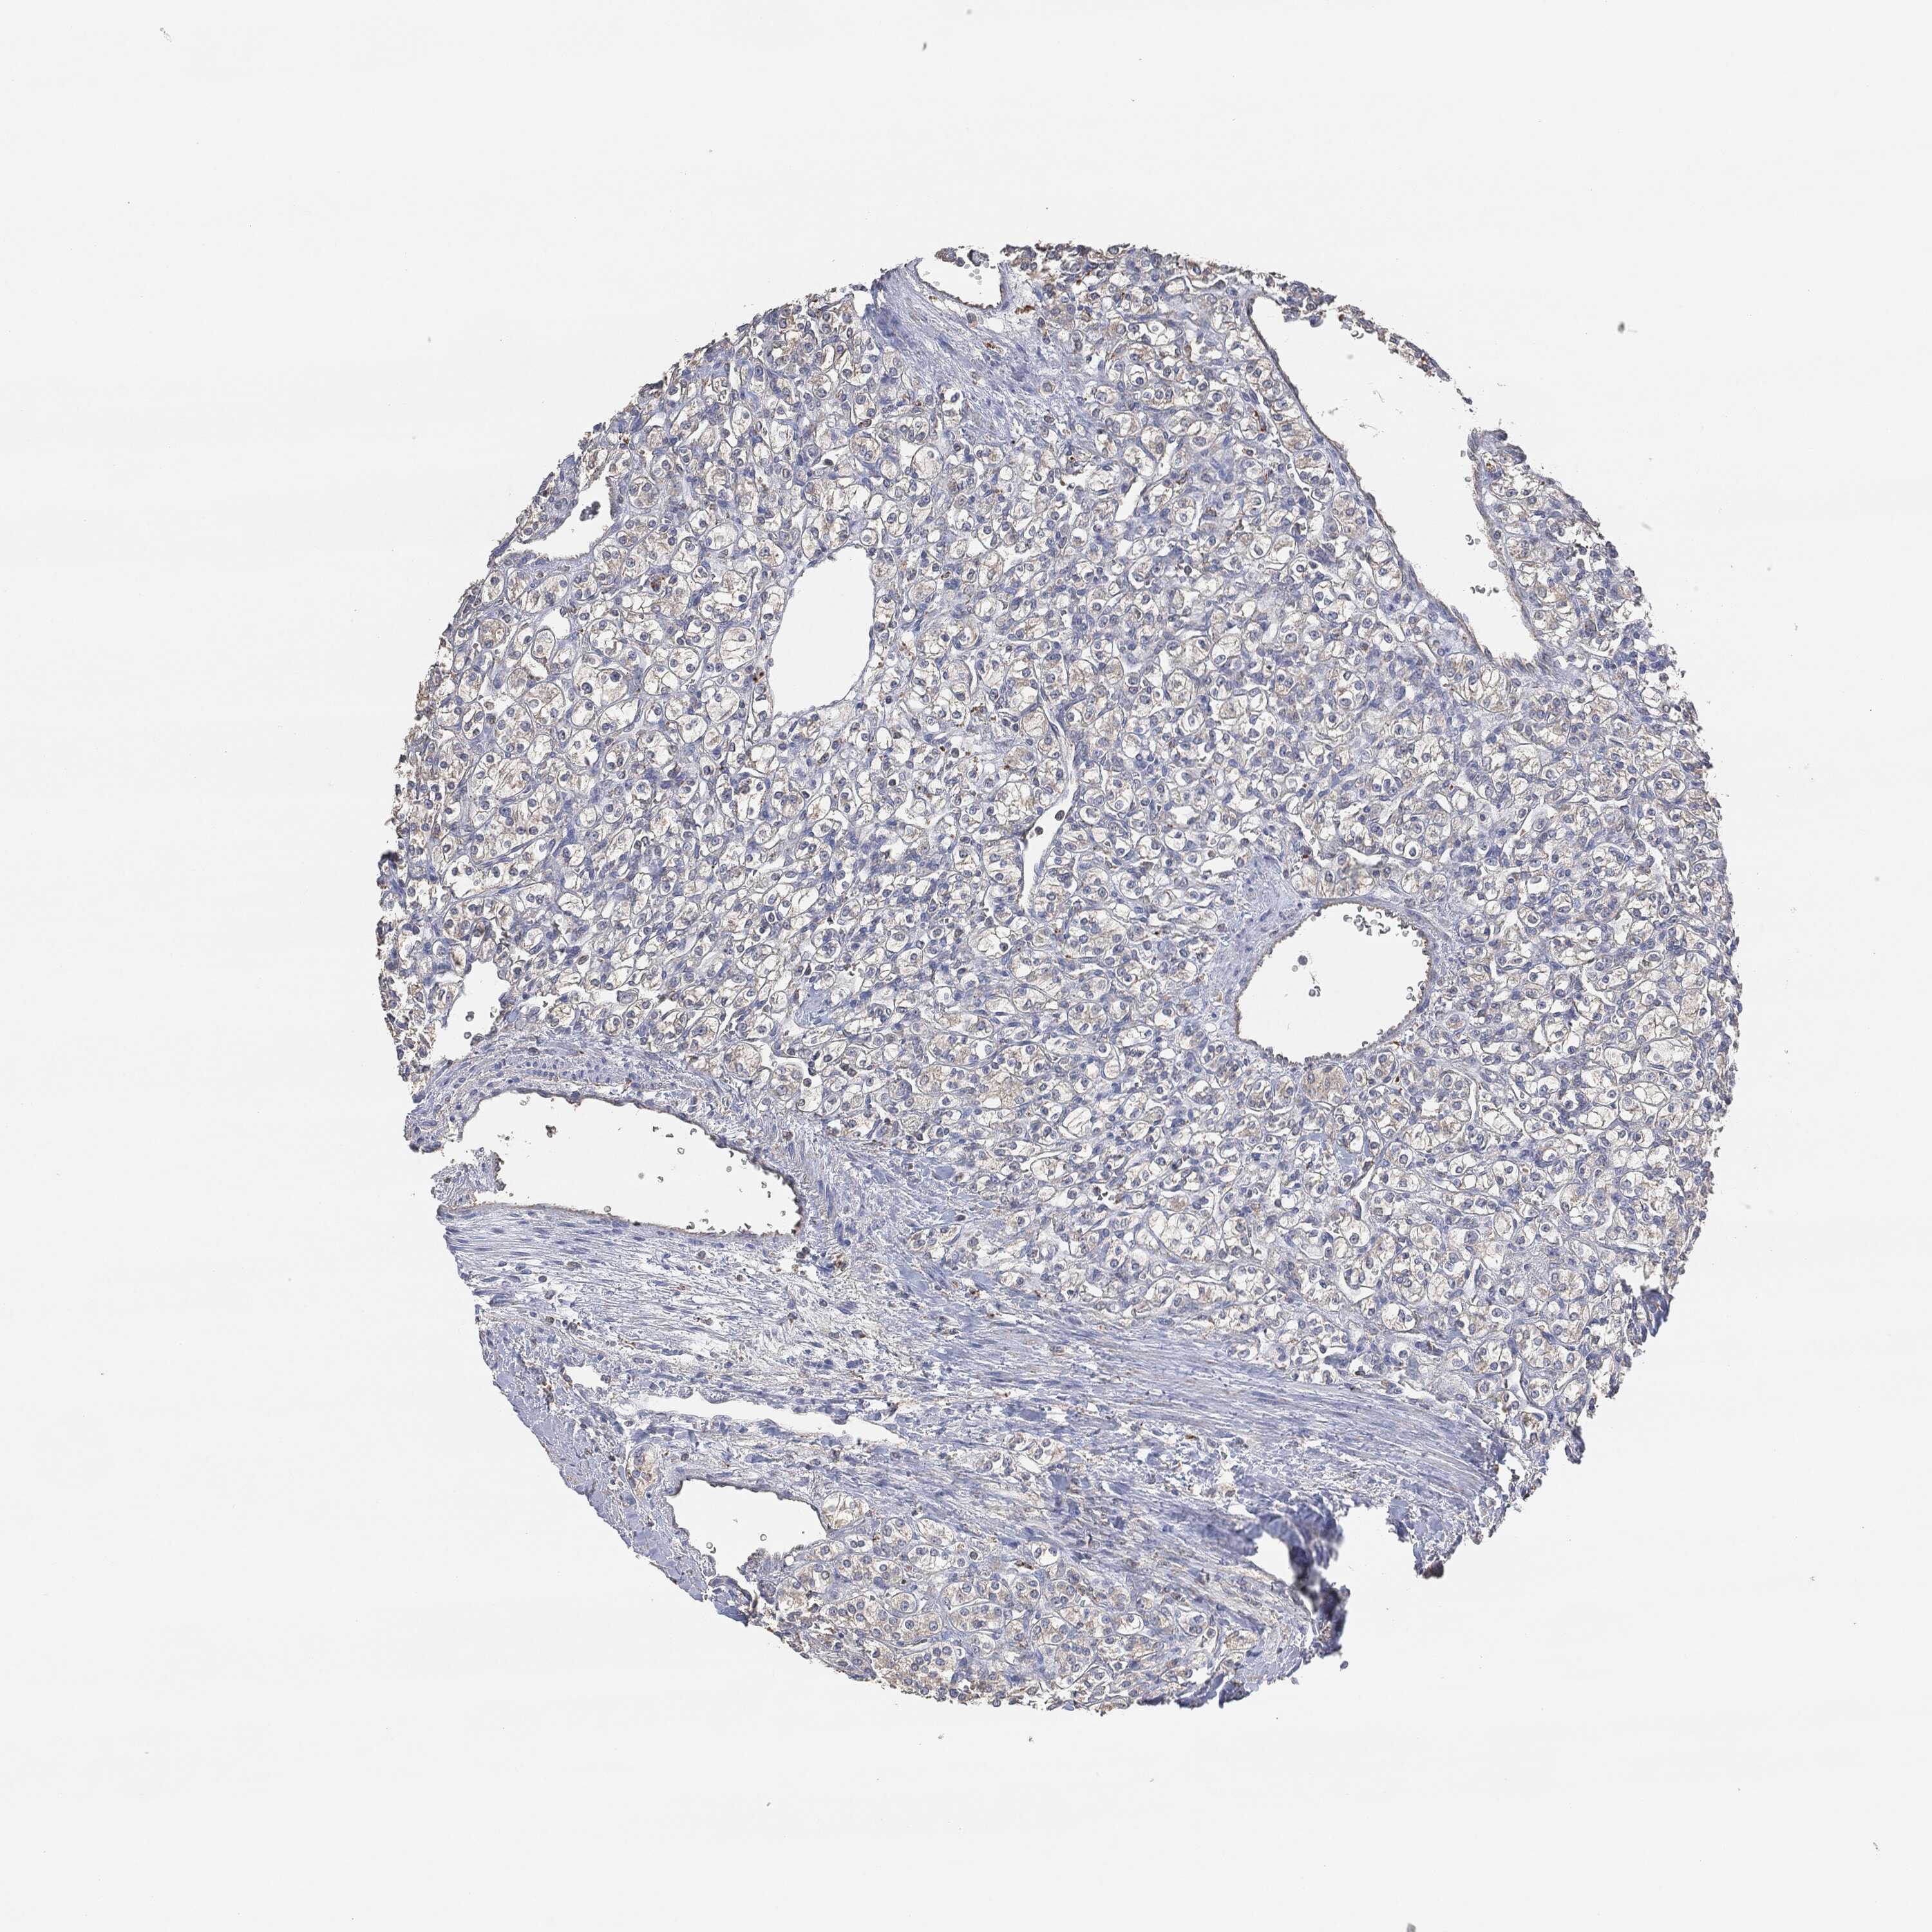

KIDNEY RENAL PAPILLARY CELL CARCINOMA (TCGA) - Interactive survival scatter ploti

The Survival Scatter plot shows the clinical status (i.e. dead or alive) for all individuals in the patient cohort, based on the same data that underlies the corresponding Kaplan-Meier plots. Patients that are alive at last time for follow-up are shown in blue and patients who have died during the study are shown in red.

The x-axis shows the expression levels (FPKM) of the investigated gene in the tumor tissue at the time of diagnosis. The y-axis shows the follow-up time after diagnosis (years). Both axes are complimented with kernel density curves demonstrating the data density over the axes. The top density plot shows the expression levels (FPKM) distribution among dead (red) and alive patients (blue). The right density plot shows the data density of the survived years of dead patients with high and low expression levels respectively, stratified using the cutoff indicated by the vertical dashed line through the Survival Scatter plot. This cutoff is automatically defined based on the FPKM cutoff that minimizes the p-score. The cutoff can be changed by dragging the vertical line or by entering a cutoff value in the square labeled "Current cut-off".

Under the Survival Scatter plot the p-score landscape (black curve; left axis) is shown together with dead median separation (red curve; right axis). Dead median separation is the difference in median mRNA expression between patients who have died with high and low expression, respectively. It is calculated as follows: median FPKM expression of dead patients with high expression - median FPKM expression of dead patients with low expression. This is intended to aid the user in visually exploring custom cutoffs and the associated p-scores and dead median separation.

Individual patient data is displayed and can be filtered by clicking on one or more of the category buttons on the top of the page. Categories describing expression level and patient information include: high, low, alive, dead, female, male and tumor stages. The scale of the x-axis can be toggled between linear and log-scale by clicking on the "x log" button. Mouse-over function shows TCGA ID, patient information and mRNA expression (FPKM) for each patient.

& Survival analysisi

Kaplan-Meier plots summarize results from analysis of correlation between mRNA expression level and patient survival. Patients were divided based on level of expression into one of the two groups "low" (under cut off) or "high" (over cut off). X-axis shows time for survival (years) and y-axis shows the probability of survival, where 1.0 corresponds to 100 percent.

EGFR is not prognostic in Kidney Renal Papillary Cell Carcinoma (TCGA)